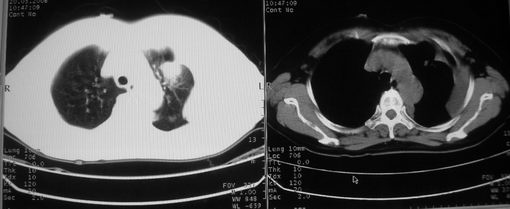

以下是引用w_jianhua在2008-5-22 12:59:00的发言:[br]1.左肺上叶肺癌并左侧胸腔积液可能性大。2不除外支气管内膜结核并包裹性胸腔积液,建议支气管镜检3.左肺下叶肺大泡,肺气肿